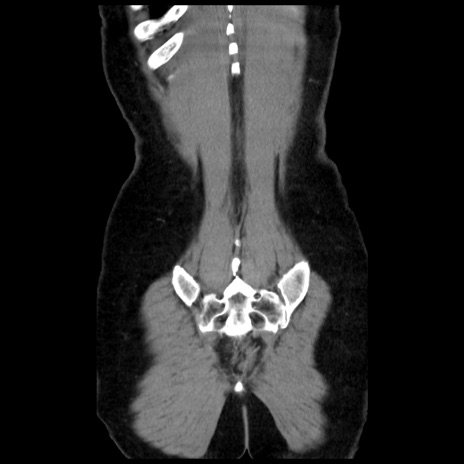

症例10(冠状断像)

【症例】 50歳代女性

【主訴】 腹痛

【現病歴】前日生レバーを食べた。今朝に排便あり。 昼前に突然発症の腹痛を生じ、当院救急外来を受診した。

【既往歴】 子宮筋腫にてで子宮全摘後

【身体所見】 意識清明、腹部:平坦、軟、下腹部やや左を中心に圧痛・反跳痛あり、筋性防御あり

【データ】WBC 7800、CRP 0.07